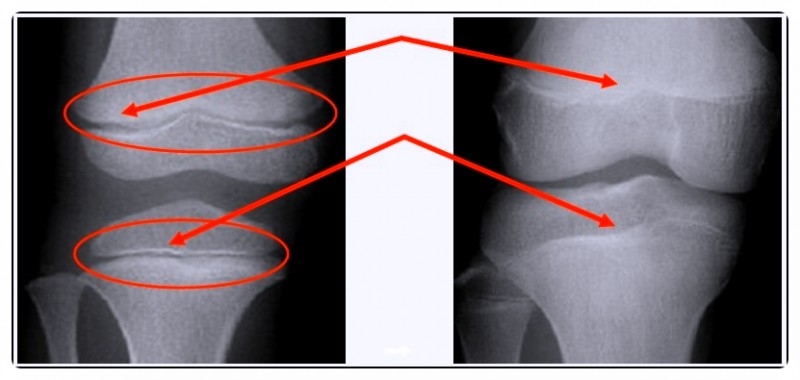

단순히 키와 체중만 보는 게 아니라, 성장판의 상태와 성조숙증 가능성, 비만 여부까지 함께 확인합니다.

성장판이 얼마나 남아 있는지에 따라 앞으로의 성장 가능성을 예측할 수 있습니다.

또래보다 체중이 빠르게 늘거나 비만인 경우, 성장판이 빨리 닫힐 위험도 커지죠.